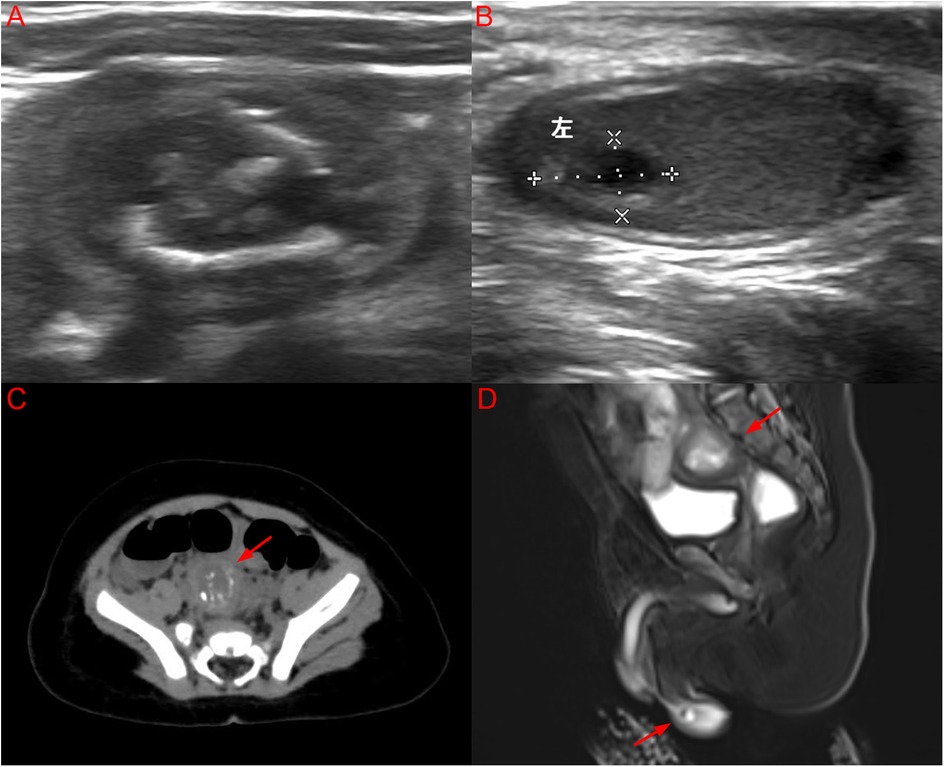

Background: Bilateral testicular tumors in infants are extremely rare. This case report describes synchronous bilateral mature teratomas complicated by torsion of an intra-abdominal undescended testis (IAT), and underscores the clinical importance of early diagnosis, timely surgical intervention, and fertility-preserving management, providing valuable reference for future cases. Case presentation: A 3-month-old boy presented with an empty right hemiscrotum. Imaging revealed a right intra-abdominal mass (22.8×15.9×21.3mm) and left testicular lesion (7.1×3.9×7.0mm). Serum alpha-fetoprotein was within normal limits for age, suggesting benign disease. Laparoscopy confirmed a torsed necrotic right testicular mass, managed by orchiectomy. Left testis-sparing surgery excised a separate tumor. Histopathology confirmed bilateral mature teratoma. Hormonal profiles, including testosterone (0.81 ng/mL) and follicle-stimulating hormone (3.74 mIU/mL), as well as karyotype (46,XY), were normal. No additional therapy was required, as mature teratomas are benign. Postoperative alpha-fetoprotein levels normalized, with no recurrence at 6-month follow-up. Parental education regarding testicular examination is important for early detection of future abnormalities. Conclusions: Tumors associated with intra-abdominal undescended testes warrant urgent intervention due to torsion risk. Surgery preserving testicular tissue is recommended for bilateral benign teratomas to maintain fertility. Serial alpha-fetoprotein monitoring and ultrasound surveillance are essential postoperatively.